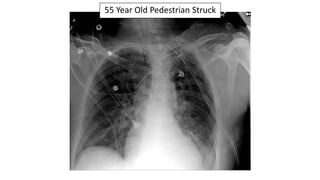

55 Year Old

Pedestrian Struck

Wide Mediastinum

Tracheal Deviation

And Loss Of The

Aortopulmonary

Window

Traumatic Aortic Disruption & Multiple Rib Fractures